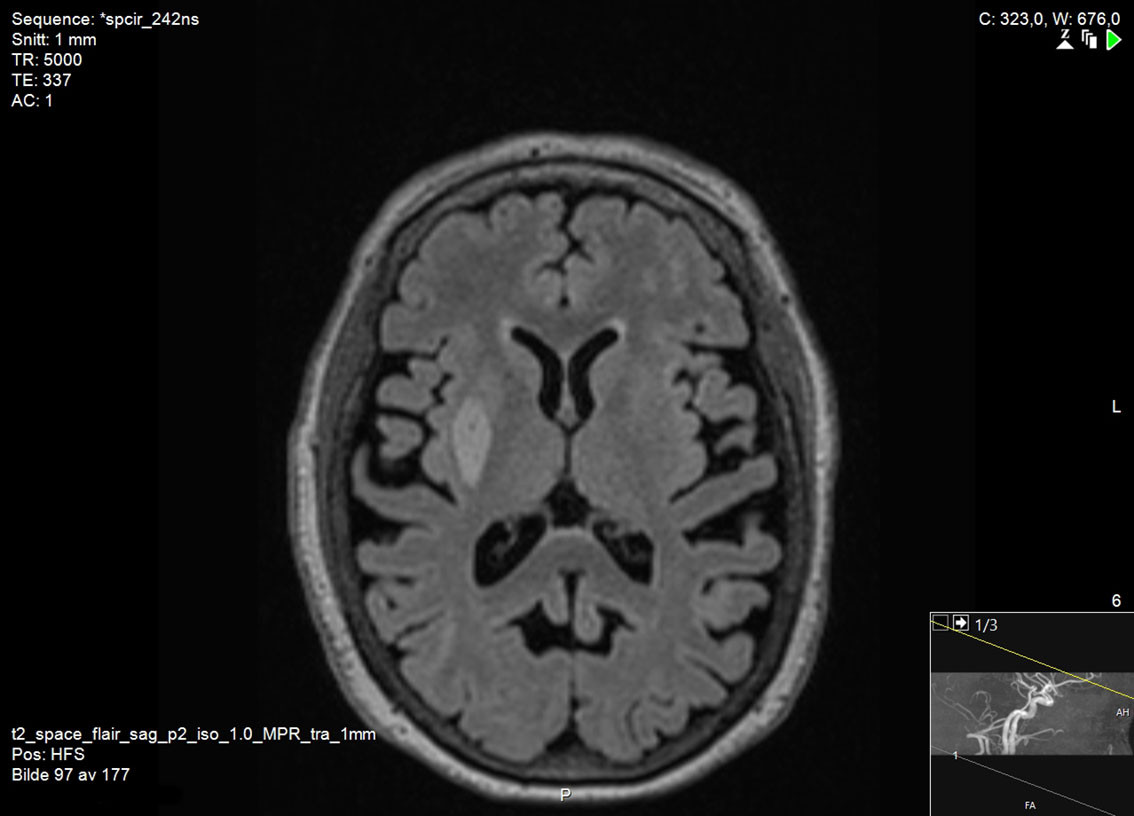

There are no universally accepted guidelines for the diagnosis of vascular parkinsonism, but based on clinical findings and pathology, Zijlmans et al. have proposed the following criteria: a) parkinsonism, b) cerebrovascular disease visible on MRI or CT, and c) a relation between a) and b), either in the form of acute hemiparkinsonism resulting from infarction or haemorrhage in the nigrostriatal pathway (subtype 1), or small vessel disease in the white matter with gradual development of parkinsonism (subtype 2) (15). Typically, brain MRI is necessary to determine whether there is damage to the nigrostriatal pathway (Figure 1) or small vessel disease in the white matter (Figure 2). CT scans of the brain are less suitable for making the diagnosis due to their lower sensitivity for lacunar infarcts and small vessel disease (5).

Differences between vascular parkinsonism and Parkinson's disease are also seen on brain imaging. In cases of vascular parkinsonism, brain MRI will reveal infarction, haemorrhage, or signs of small vessel disease. In Parkinson's disease, brain MRI can appear completely normal, although elderly patients may have vascular changes as incidental findings; however, these will be much less abundant than in cases of vascular parkinsonism (20, 21). A dopamine transporter scan (DaTSCAN) is a nuclear medicine procedure that shows changes in brain dopaminergic activity, and that can be used to detect degeneration of nigrostriatal nerve endings. DaTSCAN always shows pathological changes in Parkinson's disease, whereas in cases of vascular parkinsonism DaTSCAN is often normal if the nigrostriatal pathway is not directly affected (5).

Vascular parkinsonism is a controversial diagnosis for a number of reasons. One is that asymptomatic infarcts in the basal ganglia and white matter are very common. Among 219 adults who sought medical attention for possible cerebrovascular disease, 40.2 % were found to have silent infarcts in these regions on MRI (26). Moreover, many patients with Parkinson's disease also have cerebral vascular lesions (17). It is uncertain whether these contribute to disease development, and the boundary between vascular parkinsonism and Parkinson's disease can in some cases be unclear. In addition, we do not know for certain what pathological changes underlie the hyperintensities seen on MRI (27). Such changes are often considered to reflect small vessel disease, but inflammation accompanying demyelination and neurodegeneration can give rise to similar changes (28). Finally, the clinical presentation of vascular parkinsonism may overlap with that of conditions such as normal pressure hydrocephalus and vascular leukoencephalopathy. These latter conditions can both give rise to the combination of parkinsonism, cognitive impairment and urinary incontinence. Some have therefore argued that vascular parkinsonism is not an independent diagnosis (8, 9, 29). However, normal ventricular size and preserved cognition can help distinguish patients with vascular parkinsonism from those with normal pressure hydrocephalus and vascular leukoencephalopathy, respectively.